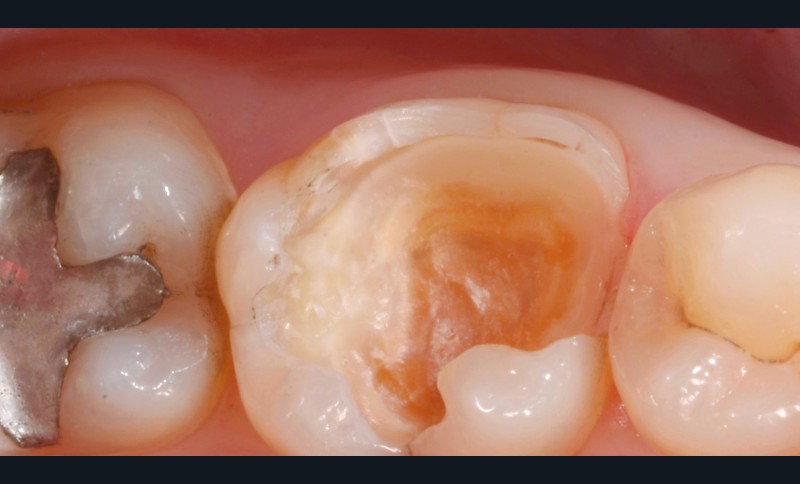

Lors de la préparation d’une cavité pour inlay/onlay, il est fréquent d’être confronté, en fin de nettoyage, à la présence d’une ou plusieurs parois résiduelles dont la résistance mécanique paraît douteuse du fait de leur localisation ou de leur épaisseur. Les parois épaisses (+ de 2 mm) peuvent généralement être conservées (cas clinique 1) et les parois fines (- de 1 mm) doivent généralement être recouvertes. Un inlay (en composite ou en céramique) est alors réalisé. Il doit avoir lui même, au final, une épaisseur globale minimale de 2 mm pour assurer sa résistance mécanique intrinsèque à la mastication. Si un recouvrement cuspidien est indiqué, la réduction occlusale doit donc se faire sur 2 mm de hauteur au minimum [1, 2].

Mais qu’en est-il des parois résiduelles d’épaisseur intermédiaire (entre 1 et 2 mm) (cas clinique 2) ?